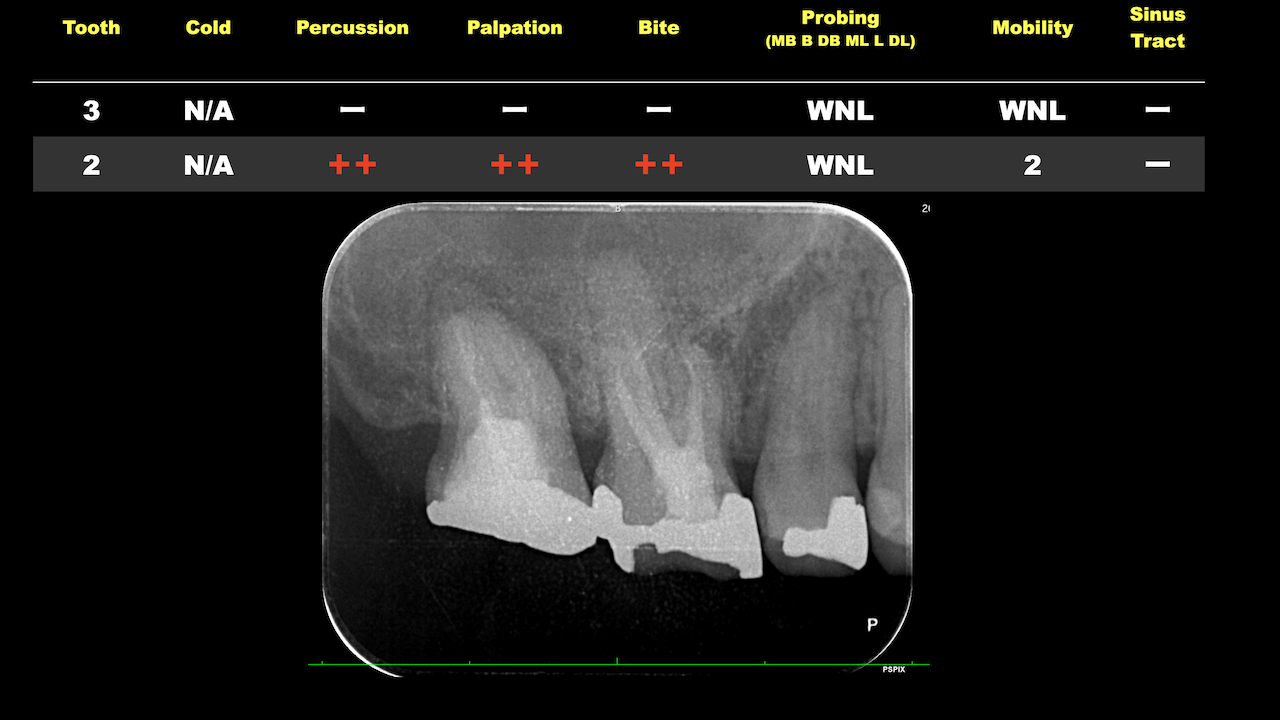

#10のRCTと3M recallである。

#9,10と病変があるが、

#9はColdに2秒で反応し、その痛みが5秒でおさまったことから生活歯と判断し、

Cold, EPTに反応がなく打診痛もある#10を患歯と考え、#10のみ根管治療することとなった。

その際の成功率は86%である。

と術前に患者さんに告げて治療へ導入し以下のようになった。

3ヶ月しか経過していないが根尖病変は大きく減少した。

治療していない#9には変化があまりないがだからと言って手をつける必要性はない。

患者に症状がないからだ。